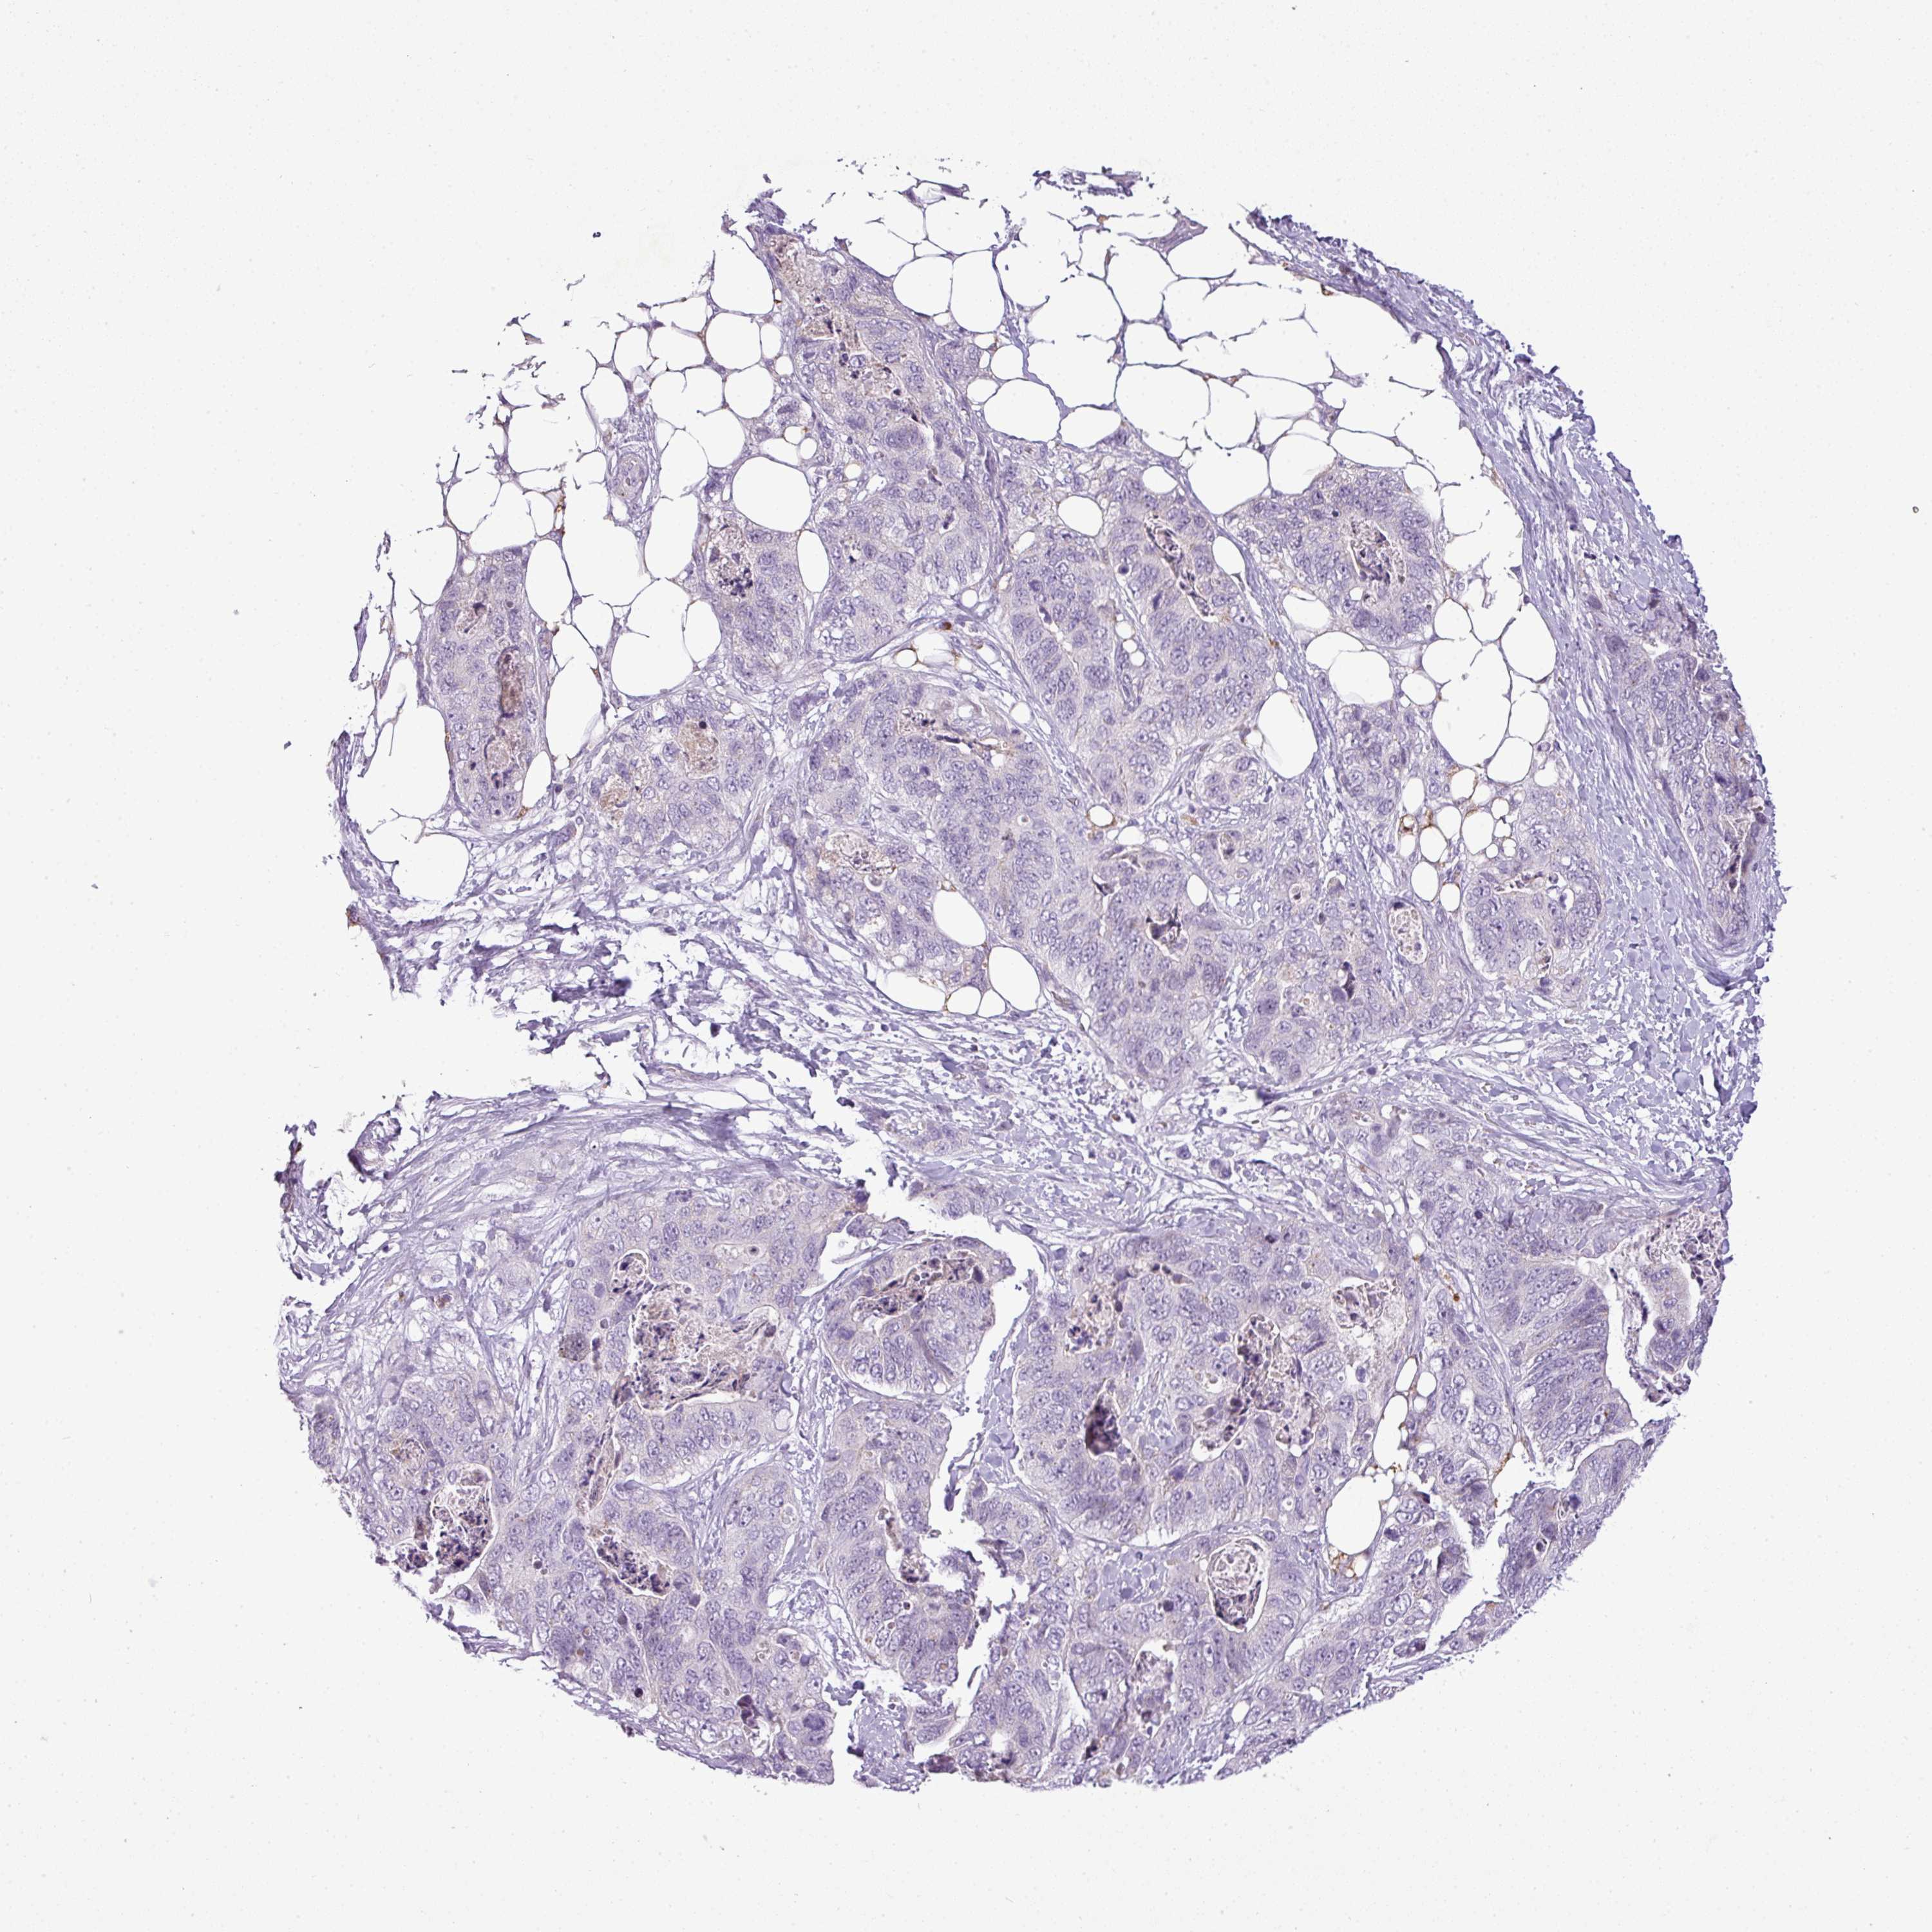

STOMACH CANCER - Protein expressioni

A mouse-over function shows sample information and annotation data. Click on an image to view it in a full screen mode. Samples can be filtered based on level of antibody staining by selecting one or several of the following categories: high, medium, low and not detected. The assay and annotation is described here.

Note that samples used for immunohistochemistry by the Human Protein Atlas do not correspond to samples in the TCGA dataset.

Antibody stainingi

Antibody staining in the annotated cell types in the current human tissue is reported as not detected, low, medium, or high, based on conventional immunohistochemistry profiling in selected tissues. This score is based on the combination of the staining intensity and fraction of stained cells.

Each image is clickable and will lead to virtual microscopy that enables deeper exploration of all samples and also displays staining intensity scores, fraction scores and subcellular localization as well as patient and tissue information for each sample.

Adenocarcinoma, NOS